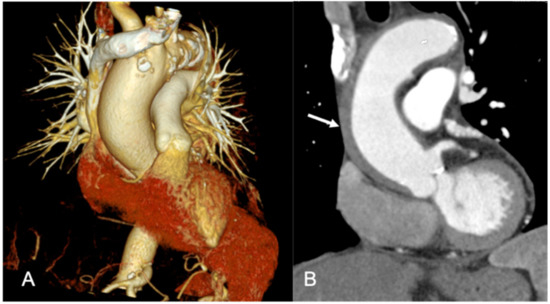

- Marano, R.; Rovere, G.; Savino, G.; Flammia, F.C.; Carafa, M.R.P.; Steri, L.; Merlino, B.; Natale, L. CCTA in the diagnosis of coronary artery disease. Radiol. Med. 2020, 125, 1102–1113. [Google Scholar] [CrossRef]

- Busse, A.; Cantré, D.; Beller, E.; Streckenbach, F.; Öner, A.; Ince, H.; Weber, M.A.; Meinel, F.G. Cardiac CT: Why, when, and how: Update 2019. Radiologe 2019, 59. [Google Scholar] [CrossRef]

- Eltabbakh, A.R.; Dawoud, M.A.; Langer, M.; Moharm, M.A.; Hamdy, E.A.; Hamisa, M.F. ‘Triple-rule-out’ CT angiography for clinical decision making and early triage of acute chest pain patients: Use of 320-multislice CT angiography. Egypt. J. Radiol. Nucl. Med. 2019, 50, 1–10. [Google Scholar] [CrossRef]

- Russo, V.; Sportoletti, C.; Scalas, G.; Attinà, D.; Buia, F.; Niro, F.; Modolon, C.; De Luca, C.; Monteduro, F.; Lovato, L. The triple rule out CT in acute chest pain: A challenge for emergency radiologists? Emerg. Radiol. 2021. [Google Scholar] [CrossRef]